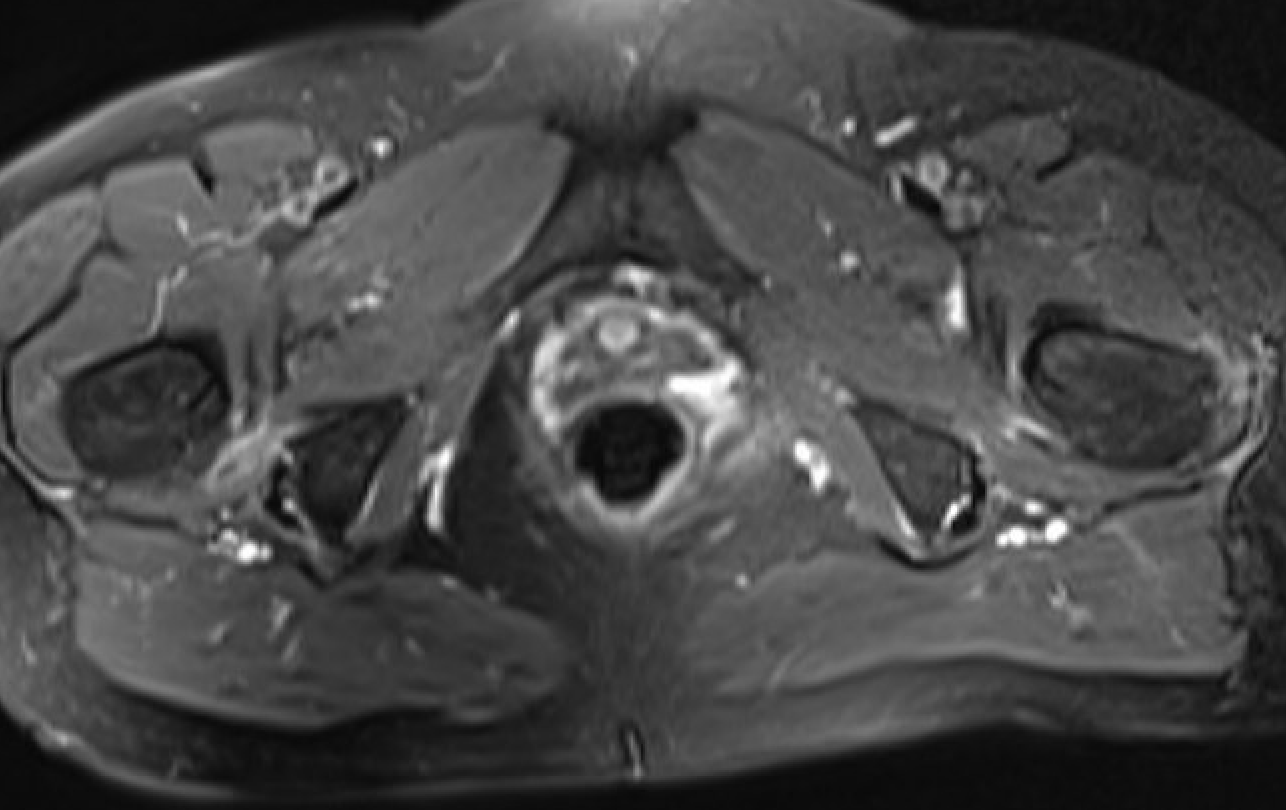

MRI

Reduced ischiofemoral space - distance between the lesser trochanter and the ischial tuberosity

Reduced quadratus femoris space - distance between hamstring tendon and iliopsoas

Inflammation / edema in quadratus femoris +/- fatty degeneration

IFIIFI

IFIIFIIFI

Singer et al Skeletal Radiol 2015

- systematic review of 190 hip MRI of patients with ischiofemoral impingement

- compared to controls

- ischiofemoral space < 15 mm: sensitivity  77%, specificity 81%, accuracy 78%

- ischiofemoral space < 10 mm: sensitivity 79%, specificity 74%, accuracy 77%.